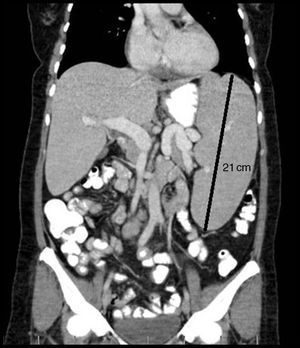

Seven years later, she presented to our department with abdominal pain and distension. We observed massive splenomegaly (Fig. 1) and persistent bicytopenia (hematocrit, 24%; leukocytes, 1000/mm3; neutrophils, 670/mm3). Laboratory results included: erythrocyte sedimentation rate, 97mm/h; RF, 47IU/mL (upper normal limit: 14IU/mL); and anti-mutated citrullinated vimentin (anti-MCV) antibodies≥300U/mL, whereas antinuclear (ANA), anti-native DNA, anti-Smith, anti-ribonucleoprotein, anti-Ro, anti-La and anticardiolipin antibodies were negative, as were cryoglobulins; her complement levels were normal. Serological tests for human immunodeficiency virus and hepatitis B and C viruses were negative. Ultrasound of both hands showed no evidence of synovitis, and radiography revealed few erosions. Biopsy showed reactive bone marrow, with hyperplasia of the granulocytic series, with no neoplastic cells; there were no signs of malignancy on flow cytometry. Given the magnitude of the splenomegaly and the absence of joint activity in recent years, we included splenic lymphoma in the differential diagnosis, and splenectomy was performed. The pathological study revealed a chronic, nonspecific, inflammatory process, and Felty's syndrome was diagnosed. Glucocorticoid therapy was begun with prednisone at 60mg/d, which was tapered over 2 years. This treatment improved the hematological signs (hematocrit, 42%; leukocytes, 3500/mm3; neutrophils, 40%), and the acute phase reactant levels were normalized.